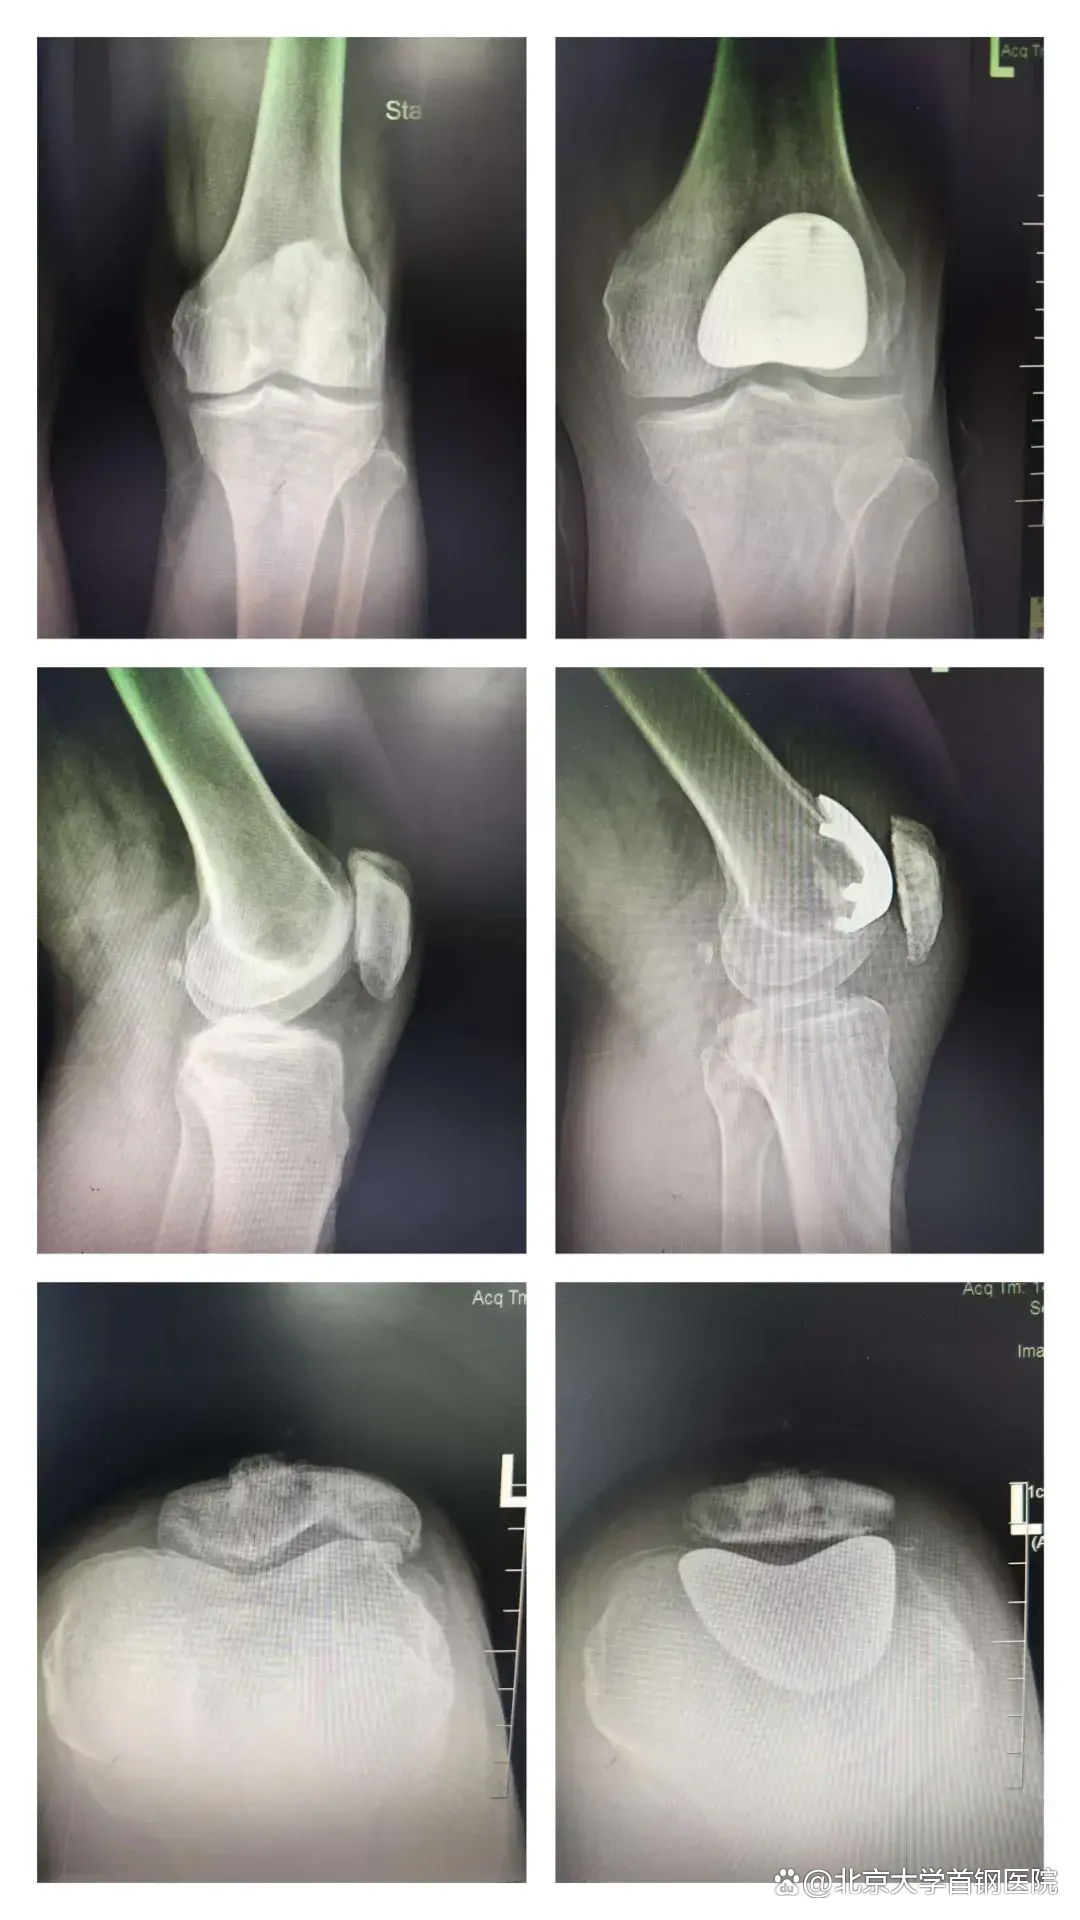

患者苏先生因为18岁髌骨粉碎性骨折后遗留创伤性髌股关节炎,病痛折磨他长达30余年,蹲起活动受限,日常生活极为不便,他辗转多家医院寻求保膝治疗方案,最终慕名来到我院的骨关节科寻求治疗。

接诊后,科室主任高度重视,立即组织医疗团队为苏先生进行全面细致的检查,明确诊断为:创伤性髌股关节炎。结合他的年龄,身体状况及病情特点,量身定制了保膝手术方案——髌股关节置换手术。

关振鹏主任亲自主刀,张辉主任、孙菁阳医生、麻醉医师及手术护士团队紧密协作、精准操作,凭借扎实的专业功底与丰富的临床经验,成功完成了这台高难度关节置换手术。